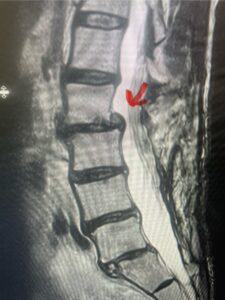

Another patient, a 77 year-old female, presents with pain, numbness, and weakness of her arms and difficulty with balance over a 6-month period. MRI revealed severe osteophytic disease at C5-C7 with cord compression (Fig. 4). Further work-up by fine-cut cervical CT to evaluate the nature of compression revealed a completely calcified osteophyte (Fig. 5). Although the patient had a good lordosis and a posterior cervical approach would accomplish an adequate decompression, we elected to perform a two-level anterior cervical discectomy and fusion. This particular osteophyte is formidable because of its size but the compression was all anterior and would be a less invasive approach. Fortunately, during the procedure, the patient had a fair amount of osteoporosis which allowed the osteophyte to be drilled and bit away with considerable ease. Interestingly, the C6 7 osteophyte which was more a sheet of osteophyte was more challenging to remove. In the end the decompression went well, and we placed two interbody devices filled with bone graft with plates at each level (Fig. 6). The patient had a nice recovery with immediate reduction of pain and numbness. This case demonstrates the importance of recognition of cervical myelopathy in its early stages. A significant reversal of function is generally the rule if the patient has appropriate correlative findings on exam and MRI, particularly with long tract distribution weakness development within a year time period.

Figs 4a: Sagittal and axial T2-weighted cervical MRIs demonstrating large osteophyte worse at C5-6 compressing spinal cord more eccentrically to the left (red arrows)

Fig 5a: Sagittal and axial cervical fine-cut CT scan demonstrating severe osteophyte formation causing cord compression at C 56 (red arrow)